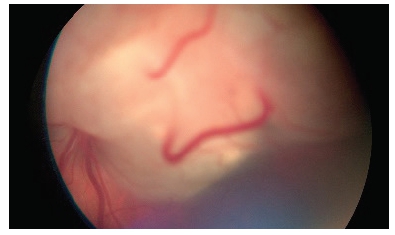

- Retinoblastomul este un tip rar de cancer ocular care afectează copiii mici, de obicei sub vârsta de 5 ani. Retinoblastomul poate afecta unul sau ambii ochi. Retinoblastomul este cancerul retinei, al structurii intraoculare unde sunt prezenți receptorii vizuali.

În unele cazuri, retinoblastomul este cauzat de o mutație genetică moștenită sau nou apărută, în această situație tumora apare la ambii ochi (bilateral). În alte cazuri nu există o genă defectă și doar un ochi este afectat (unilateral). Semnele clinice ale acestui cancer ocular sunt nespecifice și de cele mai multe ori sunt consecința scăderii vederii, astfel că adesea se manifestă prin apariția unui strabism (ochiul fuge), sau printr-un reflex alb al pupilei-leucorie. În cazuri avansate, ochiul poate fi roșu, mai mare, copilul poate avea stări de vomă, dureri de cap, afectare neurologică asociată.

Diagnosticul acestei tumori se face prin examinare oftalmologică. Stadializarea și planul de tratament se fac în urma completării cu examinarea oftalmologică în anestezie generală, completată de examen RMN. Tratamentul este multidisciplinar, general prin chimioterapie, local prin chimioterapie, radioterapie, laserterapie/chirurgical. Succesul tratamentului depinde de stadiul diagnosticului.

Retinoblastomul necesită o perioadă lungă de urmărire după tratament, cu examinări oftalmologice atente, în anestezie generală pentru a decela precoce eventualele recidive. În familiile în care există istoric de retinoblastom este necesară examinarea oftalmologică în anestezie generală, repetată, în scop de screening.

Netratat, acest tip de cancer se răspândește rapid în organism și este mortal.

Retinoblastom